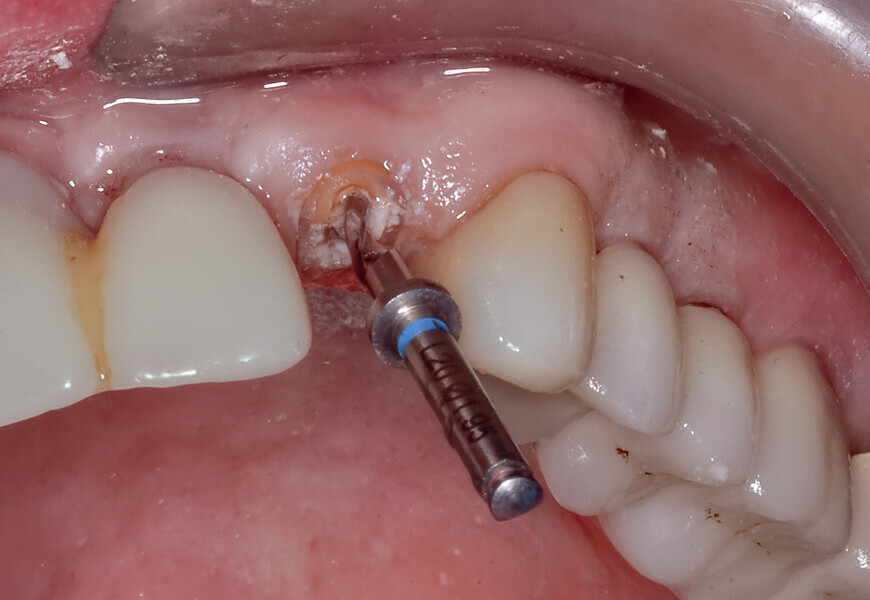

Fig. 17a: Utilising the tooth-borne template and the first insert, initial long shaper drills were used to reach the apex of the root.

Fig. 17b: Utilising the tooth-borne template and the first insert, initial long shaper drills were used to reach the apex of the root.